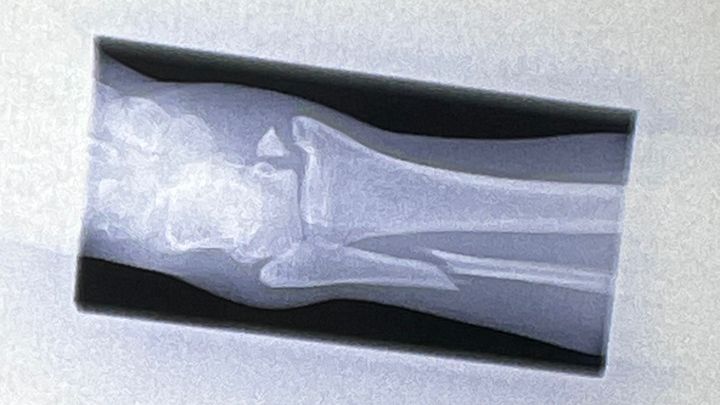

Hi, I’m Natalie and I recently broke my ankle quite severely while competing in what was supposed to be a “friendly” Judo competition. I have a trimalleolar fracture, which means my ankle is broken in 3 places and I will need surgery. I also have extensive tendon and ligament damage.